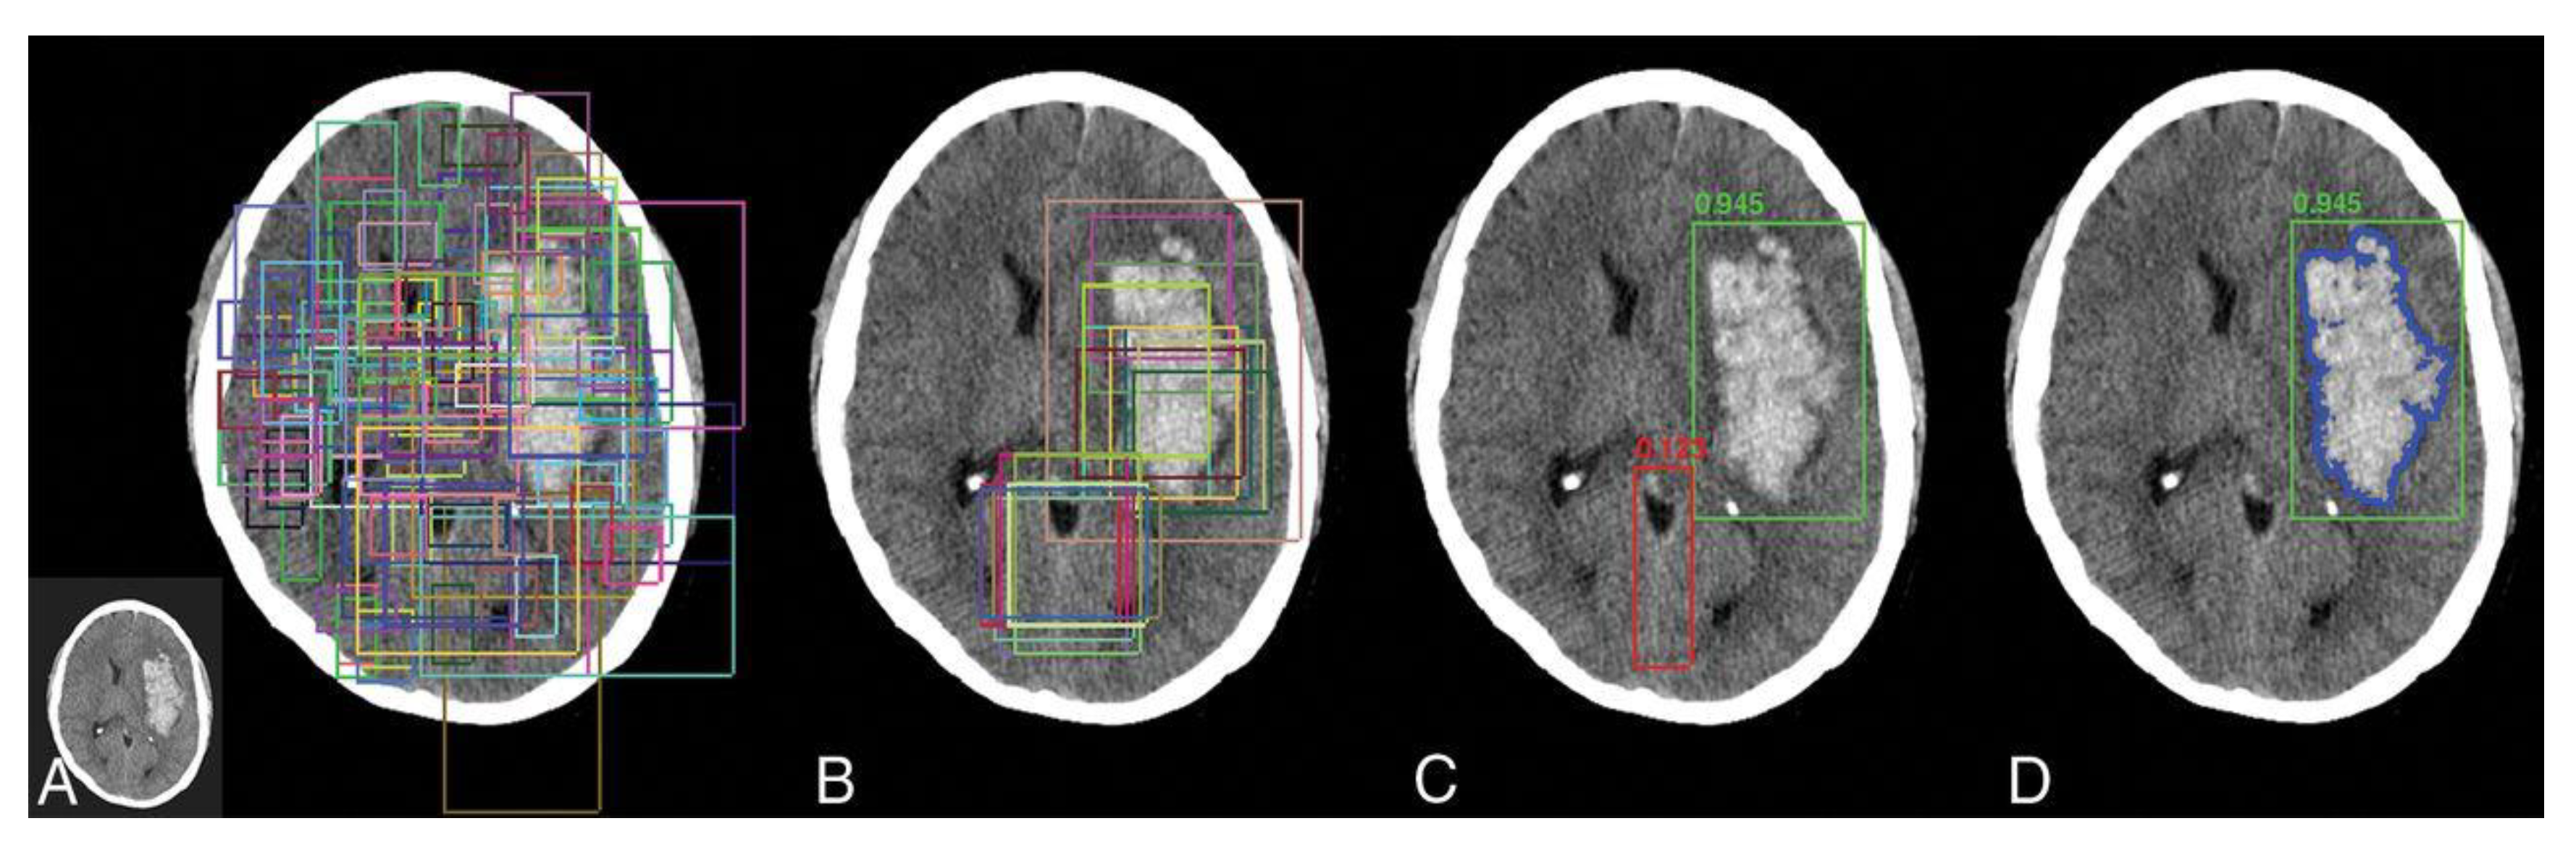

- Subudhi, A.; Acharya, U.R.; Dash, M.; Jena, S.; Sabut, S. Automated approach for detection of ischemic stroke using Delaunay Triangulation in brain MRI images. Comput. Biol. Med. 2018, 103, 116–129. [Google Scholar] [CrossRef]

| Asit et al. (2018) [114] | DWI scan | 192 images | Delaunay triangulation | Random forest | 0.93 |